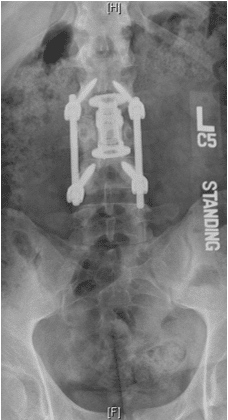

Un chico de 18 años se cayó desde tres pisos. Pérdida casi total de todas las funciones neurológicas por debajo del nivel de lesión con afectación casi total del intestino y la vejiga

Cirugía

El paciente fue operado y el conducto espinal limpiado de todos los fragmentos óseos. La columna vertebral se fijó de lado y la parte trasera para eliminar la inestabilidad.